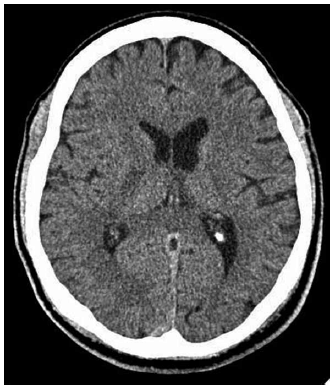

Observe a imagem e assinale a alternativa que indica qual é o local acometido pelo evento isquêmico.